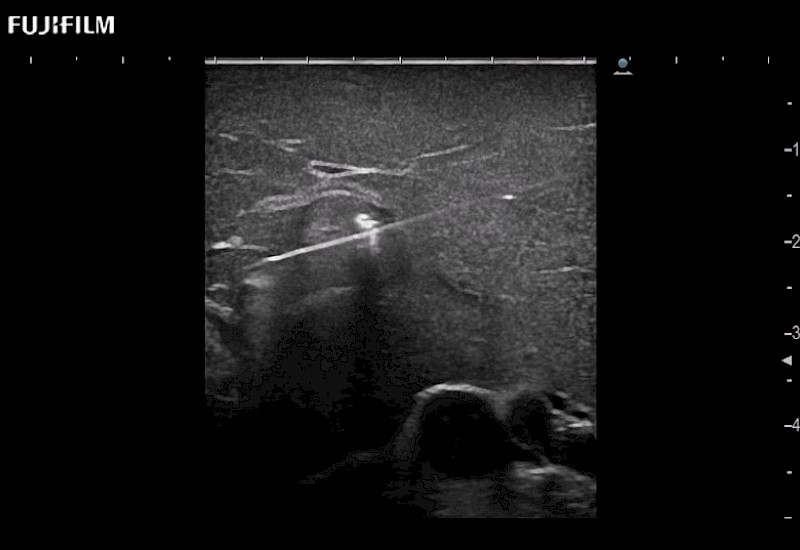

for use during open and laparoscopic procedures: Tumor localization & staging, Ablation, Resection, Biopsy, Transplant, Abdominal exploration, Robotic surgery

Needle guides and accessories

designed to work with your transducers

- Preferred transducer for liver RFA and biopsies

- Exceptional near and far-field resolution

- Instant feedback on tumor margin delineation

- Exceptional near and far-field resolution

- Instant feedback on tumor margin delineation

- Valuable information to guide tumor resections